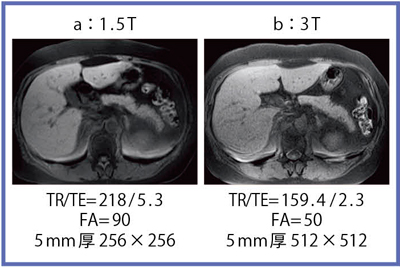

de Bazelaireらの研究1)によると,腹部領域における3Tと1.5Tの緩和時間の違いは,肝臓,脾臓,膵臓では,3TでT1値が著明に延長するのに対し,筋肉では緩和時間に差がなく,結果的に,3Tでは肝臓,膵臓,筋肉でのT1値の差が少なくなる。そこで,T1強調画像での肝臓,膵臓,筋肉の関係を検証した。図3〜5に,グラディエントエコー(GR)法を用いた,2D in-phase/out of phase,T1強調画像2D in-phase脂肪抑制像,T1強調画像3D spoiled脂肪抑制像を示す。これらの画像から,T1強調脂肪抑制像では,程度に差はあるものの,肝臓,膵臓,筋肉が同じような信号強度を示す傾向を認めた。肝臓の信号が低くなることで相対的に膵臓が白く描出される場合の主な病態としては,脂肪肝,肝硬変などがある。

次に,造影能については,T1値を短縮させる緩和試薬(Gd系)の効果が高いことから,高分解能の造影T1強調画像が期待される。図6は,肝細胞がん(HCC)におけるGd-EOB-DTPAの造影能の比較であるが,3Tでは高分解画像でも良好なCNRを保ち,肝硬変での肝実質における不均一性も表現できている。

図3 2D GR in-phase/out of phase像

脂肪を含むHCC。in-phase,out of phaseとも,

肝臓,膵臓,筋肉の信号差は著明でない。